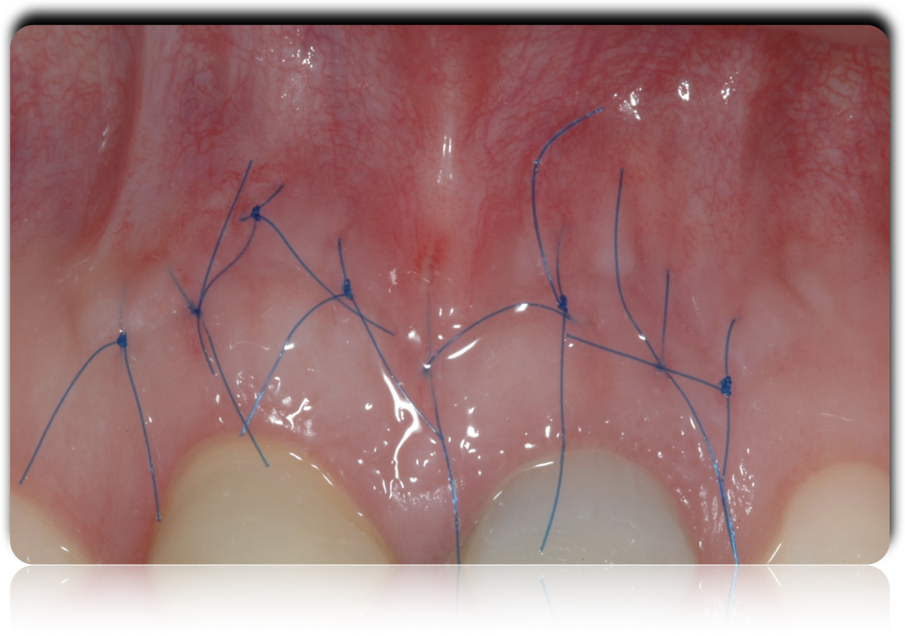

Fig. 7 - La sutura al termine dell’intervento.